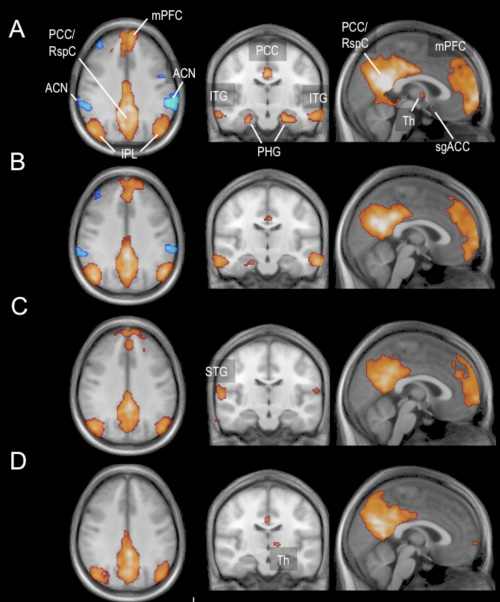

Los cambios en las redes neuronales fueron examinados dinámicamente en periodos de 26 minutos. Expansión del «sistema de modo por defecto» (en rojo) y la red anticorrelacionada (ACN, en azul) durante cuatro estados de vigilancia: A: estado de vigilia, B: estado de sueño 1, C: estado de sueño 2, D: sueño profundo. La parte prefrontal (el lóbulo prefrontal medio mPFC) pierde las conexiones a la red neuronal de manera especial. La red anticorrelacionada se debilita durante el estado de sueño 1, mientras que en el estado de sueño 2 no se detecta.

En el ámbito de la investigación, se ha demostrado que no sólo ambos sistemas de la red neuronal cambian notablemente cuando nos quedamos dormidos, sino que sus cambios de interacción también. Dependiendo del estado de sueño, el «sistema de modo por defecto» pierde parte de sus conexiones anatómicas. En particular, partes de la formación del hipocampo se separan de la red neuronal durante el sueño ligero.

Según se incrementa la profundidad en el sueño, el lóbulo prefrontal también pierde sus conexiones a la red. También reducidas, si bien es cierto que en el sueño profundo, se pueden apreciar las áreas dentro del cíngulo posterior y dentro del precuneo, una parte del lóbulo parietal. Estas zonas poseen una de las conexiones más estrechas en el cerebro. Están relacionadas con la conciencia y son influenciables en sus actividades mediante la sedación médica.

El relativo decline de la actividad en el «sistema de modo por defecto» durante el sueño, explica por qué no somos capaces de percibir conscientemente en ese estado. La red anticorrelacionada se desvincula de su actividad estrictamente opuesta desde el estado de sueño 2 en adelante, permaneciendo presente no obstante durante todos los estados de sueño. Esto indica presumiblemente que sólo la suficiente sincronización entre diferentes redes neuronales permite funciones complejas, y así puede manejar en cualquier momento un estímulo que nos despierte.